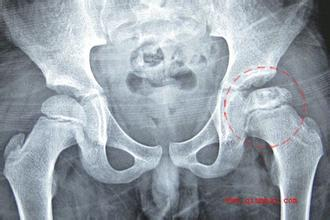

图A:X射线片为正位股骨头,股骨头内不规则高密度影;

此外,MRI片上坏死面积较术前明显减小,治疗前坏死面积为(31.0±5.3)mm2,治疗后为(24.3±3.5)mm2,具有差别意义。